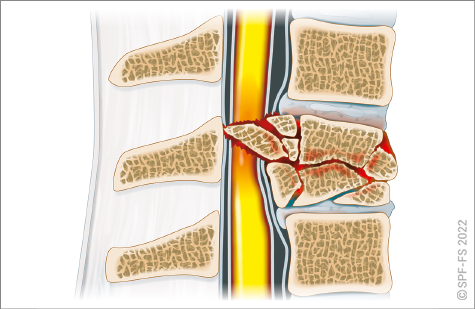

La colonne vertébrale, ou rachis, est un empilement de 33 ou 34 os articulés : les vertèbres. Elle supporte la tête et transmet le poids du corps jusqu'aux articulations des hanches. C'est sur la colonne vertébrale que sont fixées la partie arrière des côtes. Le rachis, qui contient et protège la moelle épinière, est traditionnellement divisé en cinq zones :

Figure 2-9 : la colonne vertébrale